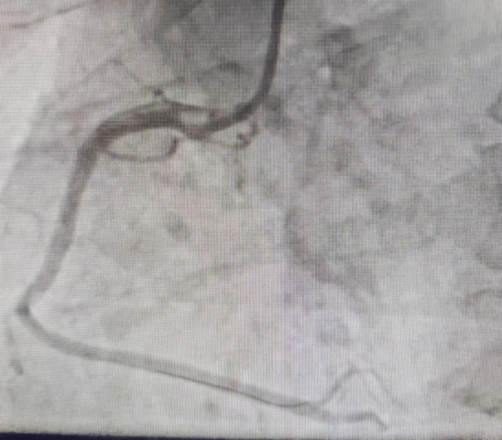

该患者右冠状动脉中段严重狭窄引起患者冠脉缺血,稍活动则诱发胸闷胸痛,冠状动脉造影显示患者右冠状动脉中段狭窄90%,冠状动脉支架植入术后,右冠状动脉残余狭窄0%,患者步行回病房,未再发作胸闷胸痛等症状。(冠脉造影见下图)

术后